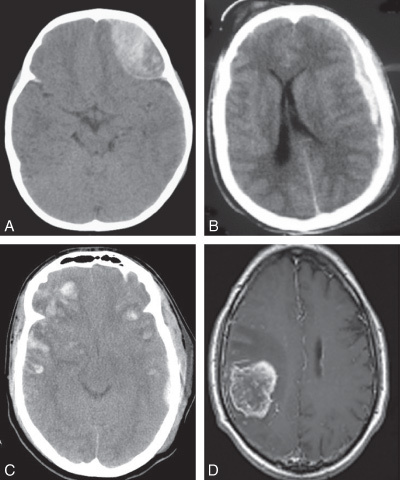

(dans l’ordre de gauche à droite et de haut en bas: abcd)

Quel diagnostic pour chaque photo?

a =hématome extradural

b=hématome sous dural

c=contusions cérébrales

d= tumeur cérébrale